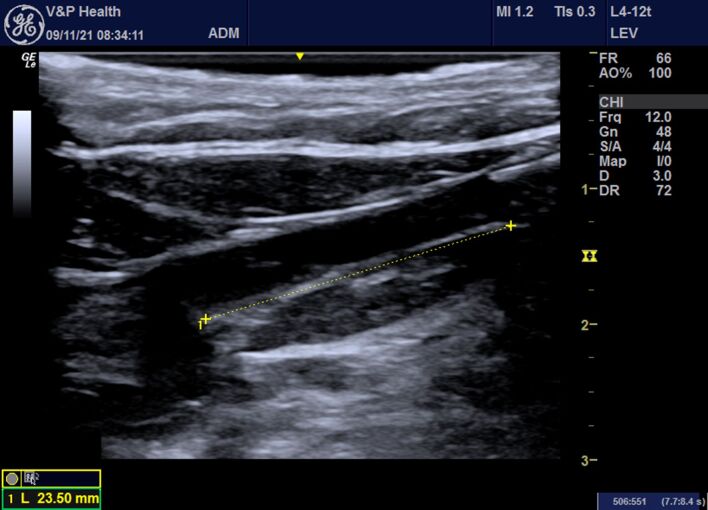

静脉腔内热消融术是目前治疗慢性静脉功能不全的最重要技术之一。技术的改进和创新使得这种方法不仅可以用于大隐静脉,还可以用于治疗浅表静脉,如静脉曲张支流。我们介绍了一种利用静脉腔内激光热消融技术进行静脉曲张手术治疗的技术,该技术采用了多次穿刺技术,并通过对 601 例使用该技术进行手术的病例进行分析,介绍了我们的服务经验。通过多个穿刺点对支静脉进行热消融治疗,扩大了腔内激光在治疗下肢静脉曲张方面的应用,提供了全面、安全和有效的治疗。

Endovenous thermal ablation is now one of the most important techniques for treating chronic venous insufficiency. Technical refinements and technological innovations have made it possible to employ the method not only in the saphenous veins, but also to treat superficial veins such as varicose tributaries. We describe a technique for surgical treatment of varicose veins using endovenous laser thermal ablation employing multiple punctures and present the experience at our service with analysis of 601 cases operated using this technique. Thermoablative treatment of tributary veins with multiple puncture sites expands the applications for endolaser in treatment of lower limb varicose veins, providing, comprehensive, safe, and effective treatment.